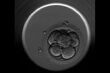

Wykorzystanie embrioskopu w procedurze zapłodnienia in vitro może zwiększyć jego skuteczność nawet o 10%. Innowacyjna amerykańska technologia jest już dostępna w białostockiej Klinice Leczenia Niepłodności "Bocian".

Lekarze z białostockiej kliniki we współpracy z Polską Akademią Nauk dowiedli, że transfer zapłodnionych zarodków do macicy ma istotny wpływ na powodzenie zabiegu in vitro. Udoskonalenie tego procesu może zwiększyć skuteczność zapłodnień.